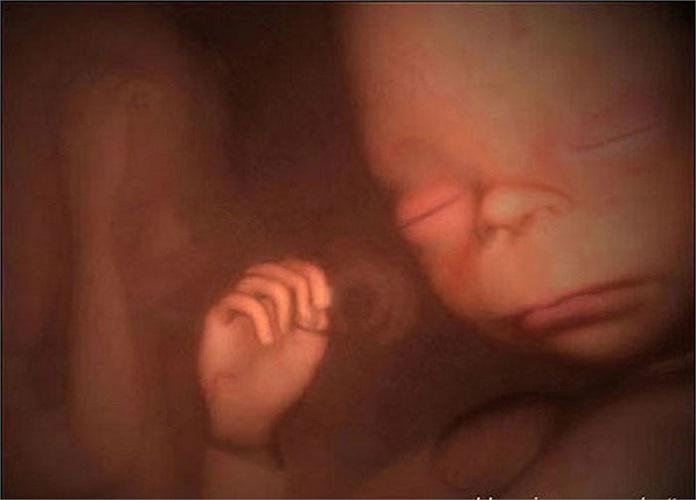

Chuyên gia sản khoa hơn 30 năm đồng hành cùng mẹ và bé

TS.BS Võ Văn Đức vừa trực tiếp theo dõi, điều trị cho thai phụ có nguy cơ cao, vừa tham gia đào tạo, nghiên cứu chuyên sâu về siêu âm và chẩn đoán trước sinh.